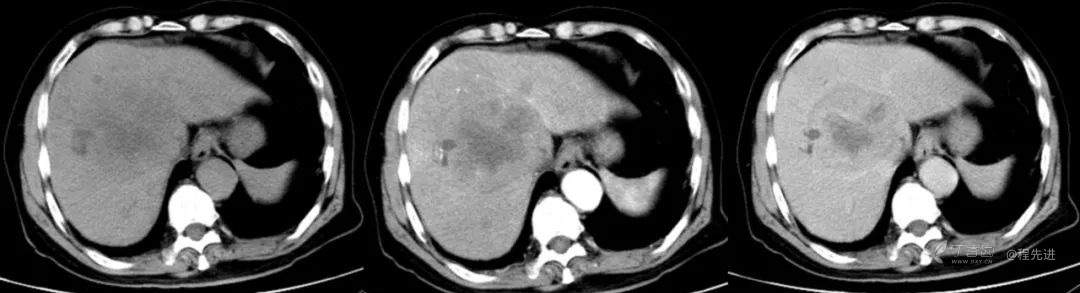

红五月特别精彩病例|胸部不适CT检查发现肝门区占位【病理已公布】

简要病史:因胸部不适入院,胸部CT示:肺部感染性病变;腹部CT示:肝门区占位性病变

既往史:有乙型肝炎病毒感染病史,未接受系统治疗

辅助检查:白细胞12.33×10^9/L 谷丙转氨酶 70u/L 谷草转氨酶90u/L